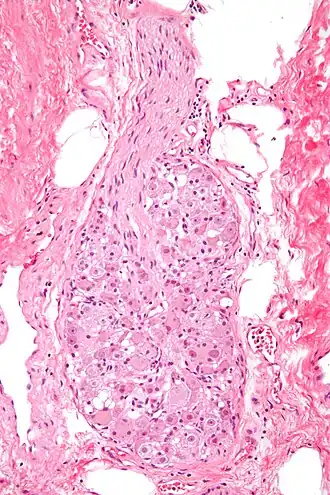

![]() Micrograph of a ganglion. H&E stain. | |

A ganglion (pl.: ganglia) is a group of neuron cell bodies in the peripheral nervous system. In the somatic nervous system, this includes dorsal root ganglia and trigeminal ganglia among a few others. In the autonomic nervous system, there are both sympathetic and parasympathetic ganglia which contain the cell bodies of postganglionic sympathetic and parasympathetic neurons respectively.

Ganglia are primarily made up of somata and dendritic structures, which are bundled or connected. Ganglia often interconnect with other ganglia to form a complex system of ganglia known as a plexus. Ganglia provide relay points and intermediary connections between different neurological structures in the body, such as the peripheral and central nervous systems.